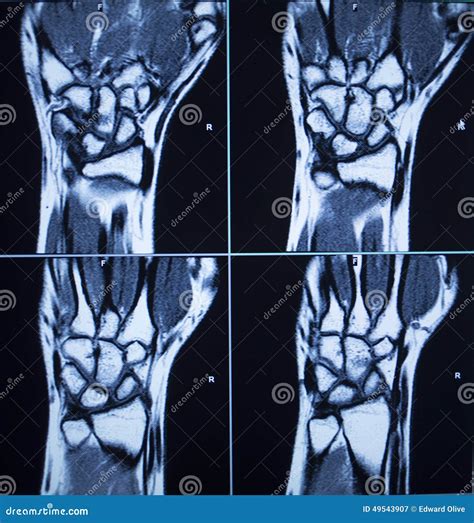

Understanding the intricacies of an MRI of hand can provide valuable insights into various hand conditions and injuries. Magnetic Resonance Imaging (MRI) is a powerful diagnostic tool that uses magnetic fields and radio waves to produce detailed images of the body's internal structures. When it comes to the hand, MRI scans offer a non-invasive way to visualize bones, muscles, tendons, ligaments, and other soft tissues with exceptional clarity.

An MRI of hand is a specialized imaging technique that focuses on the structures within the hand. This procedure is particularly useful for diagnosing conditions that affect the bones, joints, and soft tissues of the hand. Unlike X-rays, which primarily show bone structures, an MRI provides a comprehensive view of both hard and soft tissues, making it an invaluable tool for orthopedic and rheumatologic evaluations.

Interpreting MRI of Hand Results

Interpreting the results of an MRI of hand requires the expertise of a radiologist. The images will be reviewed to identify any abnormalities or conditions. Here are some key points that the radiologist will look for:

• Bone Structures: The radiologist will examine the bones for any fractures, deformities, or signs of bone diseases.

• Soft Tissues: The condition of ligaments, tendons, and muscles will be assessed for tears, inflammation, or other injuries.

• Joints: The joints will be evaluated for signs of arthritis, inflammation, or other joint-related issues.

• Nerves: The nerves will be checked for compression or other abnormalities that could cause pain or numbness.

• Tumors and Cysts: Any masses or cysts within the hand will be identified and characterized.